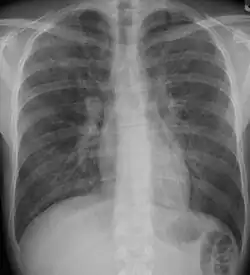

A chest X-ray demonstrating pulmonary fibrosis due to amiodarone

A chest x-ray is 63% sensitive and 93% specific for ILD.[10] With advances in computed tomography, CT scans of the chest have supplanted lung biopsy as the preferred diagnostic test for ILD. A thoracic CT scan is 91% sensitive and 71% specific for ILD.[10] In higher income countries, less than 10% of people with ILD undergo a lung biopsy as part of the diagnostic evaluation.[16]